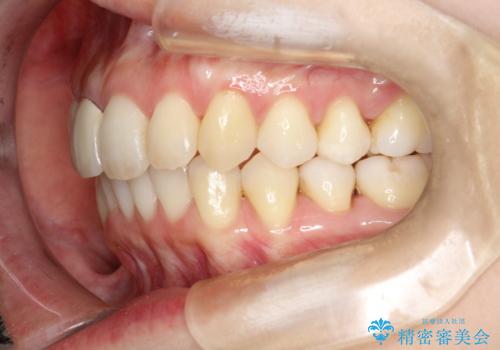

- 上下のがたつきを主訴に来院された患者様です。

上下の前歯と奥歯にがたつきがありました。

上下の奥歯を後方に移動させるのと、歯と歯の間をわずかに削ることでスペースを作り、歯を並べる計画としました。

比較的がたがたの度合いが大きかったですが、しっかりとマウスピースを使用していただけたので、順調に治療を終えることができました。